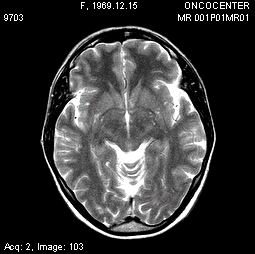

Всем пациентам в процессе курса и после брахитерапии проводили МРТ контроль в ранние сроки. Уже на 10-15 сутки после курса терапии наблюдали изменения МРТ структуры и размеров опухоли. При этом перифокальный отёк был выражен минимально ввиду особенности метода и точного подведения дозы. В дальнейшем КТ или МРТ контроль проводили через 1, 3, 6, 12 месяцев.

Описываем клинический случай стереотаксической брахитерапии, выполненной в Уральском межтерриториальном нейрохирургическом центре (ГБУЗ СО Свердловский областной онкологический диспансер), пациентке К. 31 год с глиальной опухолью диэнцефальной области (дна III желудочка). Данные МРТ головного мозга представлены на слайдах.

7. МРТ контроль спустя 4 месяца после брахитерапии. Отмечается положительная динамика в виде регресса опухоли.